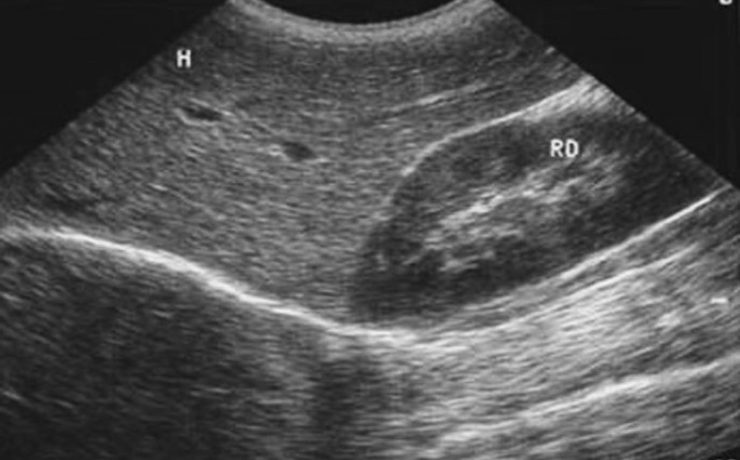

Los bultos o anormalidades en la mama generalmente se detectan por medio de un examen físico, mamografía, u otros estudios de diagnóstico por imágenes. Sin embargo, no siempre es posible detectar a través de dichos diagnósticos por imágenes si el crecimiento de los mismos es cancerígeno o benigno. Una biopsia